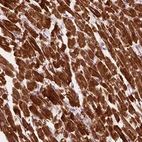

Immunohistochemical staining of human heart muscle shows cytoplasmic positivity in myocytes.